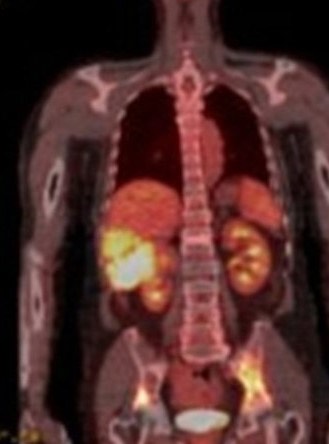

1958. Методом исследования, которому соответствует представленная томограмма, является